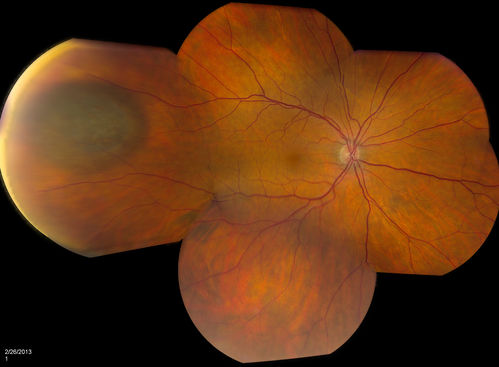

Uveal Choroidal Melanoma

Patient comes in for evaluation on a Choroidal Melanoma in the right eye. VA was 20/25 in both eyes. The melanoma is in the temporal aspect of the right eye. It measured at 0.7mm elevated after doing a BSCAN Ultrasound.

Mayo Clinic Jacksonville, Florida

TOPCON TRC 50-EX